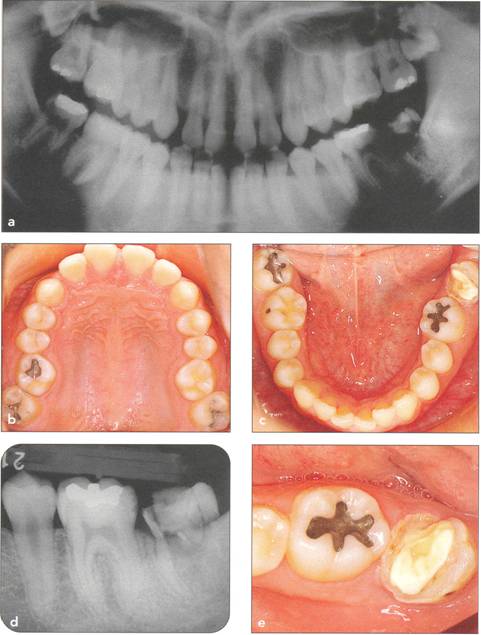

Fi 545e45f g 5-1a Preoperative panoramic view. The patient is a 24-year-old female. Transplantation of the mandibular right third molar to the area of nonrestorable mandibular first molar is planned. |

Fi 545e45f gs 5-1b and 5-1c Maxillary and mandibular teeth after initial periodontal treatment of brushing, scaling, and root planing. |

Fi 545e45f g 5-1d Preoperative periapical radiograph. |

Fi 545e45f g 5-1e Preoperative view of the donor tooth and the recipient site. |